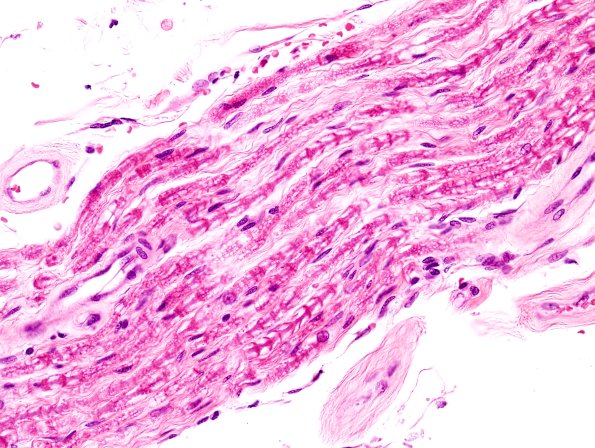

5A,B “Neurokeratin” artifact refers to the herringbone appearance of myelinated fibers in formalin-fixed longitudinal sections and is thought to represent autolysis. (H&E).